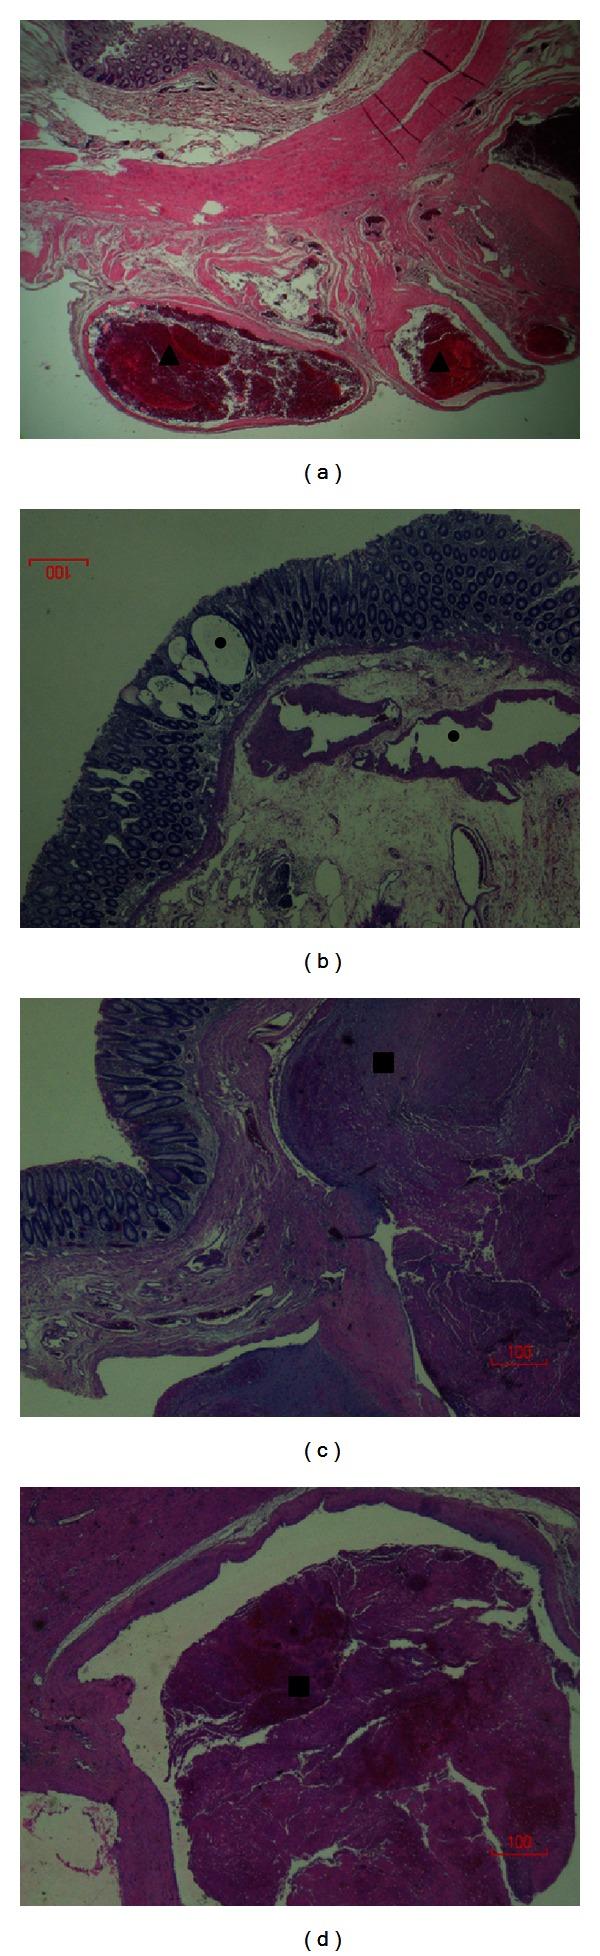

Klippel-Trenaunay syndrome (KTS) is a rare congenital syndrome of vascular malformations and soft tissue and bone hypertrophy. Vascular malformations can affect multiple organ systems. Involvement of the gastrointestinal (GI) tract is uncommon in KTS, but it can be a source of life-threatening bleeding. We report a case of a 32-year-old male with a known diagnosis of KTS who presented with a life-threatening rectal bleeding and was treated with proctosigmoidectomy and massive blood products transfusion. He expired after a long hospitalization. We then review the literature on KTS and management of some of its complications.

克-特综合征(KTS)是一种罕见的先天性综合征,伴有血管畸形以及软组织和骨骼肥大。血管畸形可累及多个器官系统。胃肠道(GI)受累在KTS中并不常见,但可能是危及生命的出血来源。我们报告一例32岁男性,已知诊断为KTS,因出现危及生命的直肠出血接受了直肠乙状结肠切除术和大量输血治疗。他在长期住院后死亡。我们随后回顾了关于KTS及其一些并发症处理的文献。